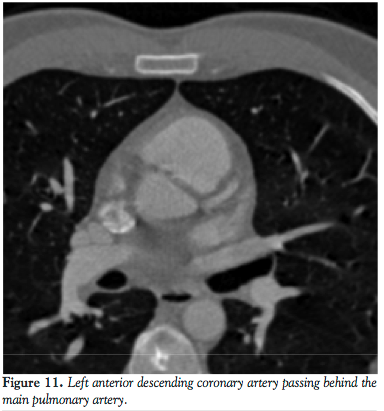

A subsequent CT angiography was obtained to delineate the course of this vessel. A 64-slice CT scan revealed that the left coronary artery coursed in between the aorta and pulmonary artery. In view of his ongoing chest pains, with a high risk of myocardial infarctions (MI), fatal arrhythmias, and sudden death, CABG was recommended.

The second case illustrates the left main coronary artery arising from the RCA and passing in between the aorta and main pulmonary trunk. This anatomy corresponds to the IIB2 classification of the isolated coronary artery anomalies.5 In this case, the risk of MI, fatal arrhythmias, syncope, and sudden death is significantly increased and it is postulated that this may occur as a result of an expansive effect of the aorta during exercise. This leads to the compression of the left coronary artery, which results in chest pains, angina, arrhythmias, and even sudden death. Our patient was found to have had a negative noninvasive work-up for coronary artery disease but in spite of this, had persistent recurrent chest pains for which coronary artery angiography was recommended.